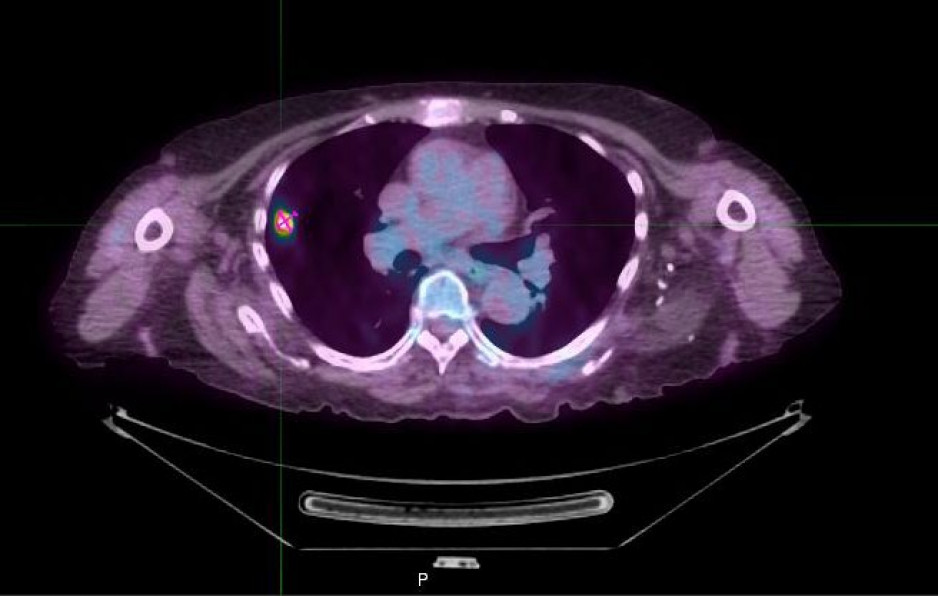

PET/CT image

A PET/CT scan provides detailed images of areas inside the body helping to detect disease.

The machine combines two imaging platforms in one. The computerized tomography (CT) scan provides an anatomical view of the body. The positron emission tomography (PET) scan shows the body’s organs and tissues at work, giving clinicians a clearer picture of their metabolic or biochemical function.

In order to pinpoint disease, such as cancer, heart disease or neurological disorders, patients are given a small amount of radioactive material combined with a carrier molecule. Called a radiotracer, it travels through the body and builds up in certain areas, revealing the location and activity of disease. This approach can also be used to assess how patients are responding to treatment.